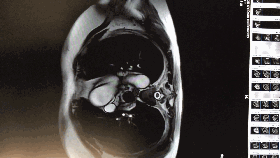

入院心脏彩超

◆左房:39;左室:48;右房:37;右室36。

◆室间隔基底部:22;肌部:16;左室后壁:11

◆心功能:FS:37%;EF:67%

◆二尖瓣前瓣收缩期前向运动致左室流出道狭窄,内径6.5mm,该处记录到收缩期湍流,压差67mmHg。

◆二尖瓣返流:6cm2;三尖瓣返流1cm2

◆结论:肥厚型梗阻性心肌病